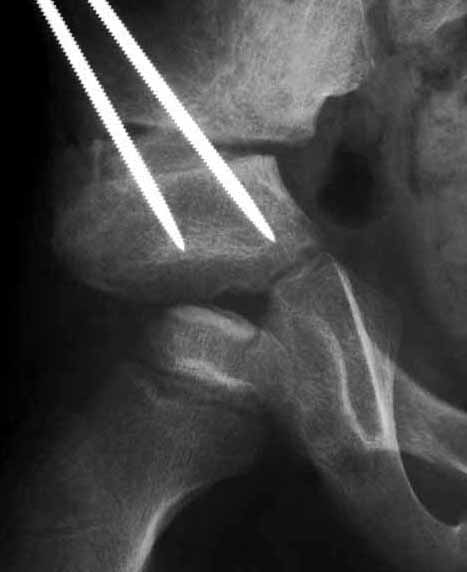

右図のように、骨盤の骨切りをおこなって十分骨頭を包み込みます。この手術のコツは、骨盤骨を広範に剥離すること、臼蓋を回転させるときに細かい技を駆使することです。この手術も慣れた術者がしなければなりません。経験上、100例くらい経験すると洗練された手術ができるようになると思います。